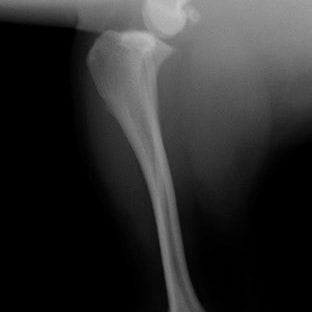

左後肢の挙上を主訴に来院されました。触診にて両関節の前方引き出し兆候、両膝蓋骨の内方脱臼を認めました。関節液検査より免疫介在性多発性関節炎は否定的でした。レントゲン検査にてfat pad signを伴う関節炎が認められたことから、前十字靭帯断裂と膝蓋骨内方脱臼(左GradeⅢ 右GradeⅢ〜IV)併発と診断し、手術を行いました。

術前左後肢側面像

術前正面像

術前のTPAは左後肢33.1°右後肢26.8°でしたがTPLO実施により左後肢5.5°右後肢12°に矯正されました。